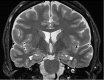

Neurodegenerative diseases are a devastating group of disorders that can be difficult to accurately diagnose. Although these disorders are difficult to manage owing to relatively limited treatment options, an early and correct diagnosis can help with managing symptoms and coping with the later stages of these disease processes. Both anatomic structural imaging and physiologic molecular imaging have evolved to a state in which these neurodegenerative processes can be identified relatively early with high accuracy. To determine the underlying disease, the radiologist should understand the different distributions and pathophysiologic processes involved. High-spatial-resolution MRI allows detection of subtle morphologic changes, as well as potential complications and alternate diagnoses, while molecular imaging allows visualization of altered function or abnormal increased or decreased concentration of disease-specific markers. These methodologies are complementary. Appropriate workup and interpretation of diagnostic studies require an integrated, multimodality, multidisciplinary approach. This article reviews the protocols and findings at MRI and nuclear medicine imaging, including with the use of flurodeoxyglucose, amyloid tracers, and dopaminergic transporter imaging (ioflupane). The pathophysiology of some of the major neurodegenerative processes and their clinical presentations are also reviewed; this information is critical to understand how these imaging modalities work, and it aids in the integration of clinical data to help synthesize a final diagnosis. Radiologists and nuclear medicine physicians aiming to include the evaluation of neurodegenerative diseases in their practice should be aware of and familiar with the multiple imaging modalities available and how using these modalities is essential in the multidisciplinary management of patients with neurodegenerative diseases.©RSNA, 2020.